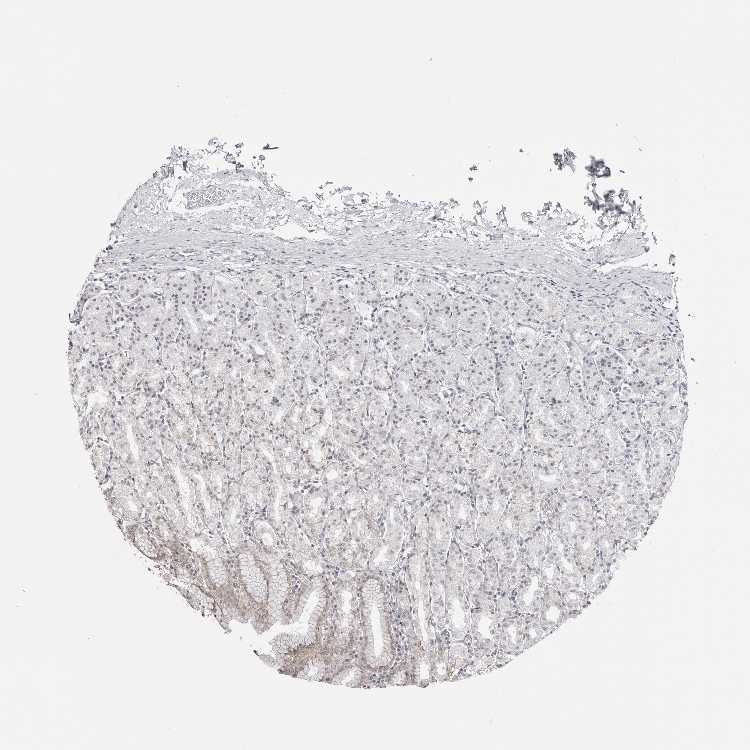

STOMACH 2 - Antibody stainingi

Antibody staining in the annotated cell types in the current human tissue is reported as not detected, low, medium, or high, based on conventional immunohistochemistry profiling in selected tissues. This score is based on the combination of the staining intensity and fraction of stained cells.

Each image is clickable and will lead to virtual microscopy that enables deeper exploration of all samples and also displays staining intensity scores, fraction scores and subcellular localization as well as patient and tissue information for each sample.

Antibody HPA026918Antibody CAB013274Antibody CAB018389

Glandular cells MediumHighMedium